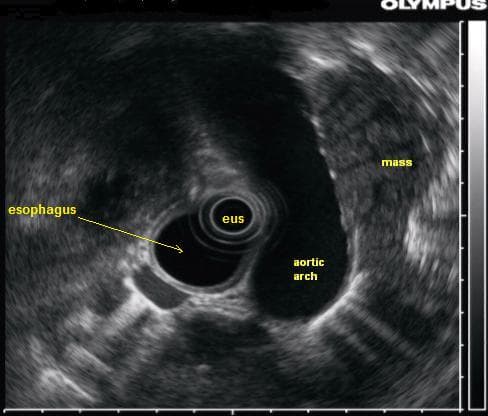

Endoscopic ultrasound (EUS) or echo-endoscopy is a medical procedure in which endoscopy (insertion of a probe into a hollow organ) is combined with ultrasound to obtain images of the internal organs in the chest, abdomen and colon. It can be used to visualize the walls of these organs, or to look at adjacent structures. Combined with Doppler imaging, nearby blood vessels can also be evaluated. Endoscopic ultrasonography is most commonly used in the upper digestive tract and in the respiratory system. The procedure is performed by gastroenterologists or pulmonologists who have had extensive training. For the patient, the procedure feels almost identical to the endoscopic procedure without the ultrasound part, unless ultrasound-guided biopsy of deeper structures is performed. For endoscopic ultrasound of the upper digestive tract, a probe is inserted into the esophagus, stomach, and duodenum during a procedure called esophagogastroduodenoscopy. Among other uses, it allows for screening for pancreatic cancer, esophageal cancer, and gastric cancer, as well as benign tumors of the upper gastrointestinal tract. It also allows for characterization and biopsy of any focal lesions found in the upper gastrointestinal tract, such as esophageal tuberculosis. This is done by inserting a needle through the stomach lining into the target. Less commonly this procedure is used to identify malformations and masses in the bile ducts and pancreatic ducts. Endoscopic ultrasound is performed with the patient sedated. The endoscope is passed through the mouth and advanced through the esophagus to the suspicious area. From various positions between the esophagus and duodenum, organs within and outside the gastrointestinal tract can be imaged to see if they are abnormal, and they can be biopsied by a process called fine needle aspiration. Organs such as the liver, pancreas, and adrenal glands are easily biopsied, as are any abnormal lymph nodes. In addition, the gastrointestinal wall itself can be imaged to see if it is abnormally thick, suggesting inflammation or malignancy.